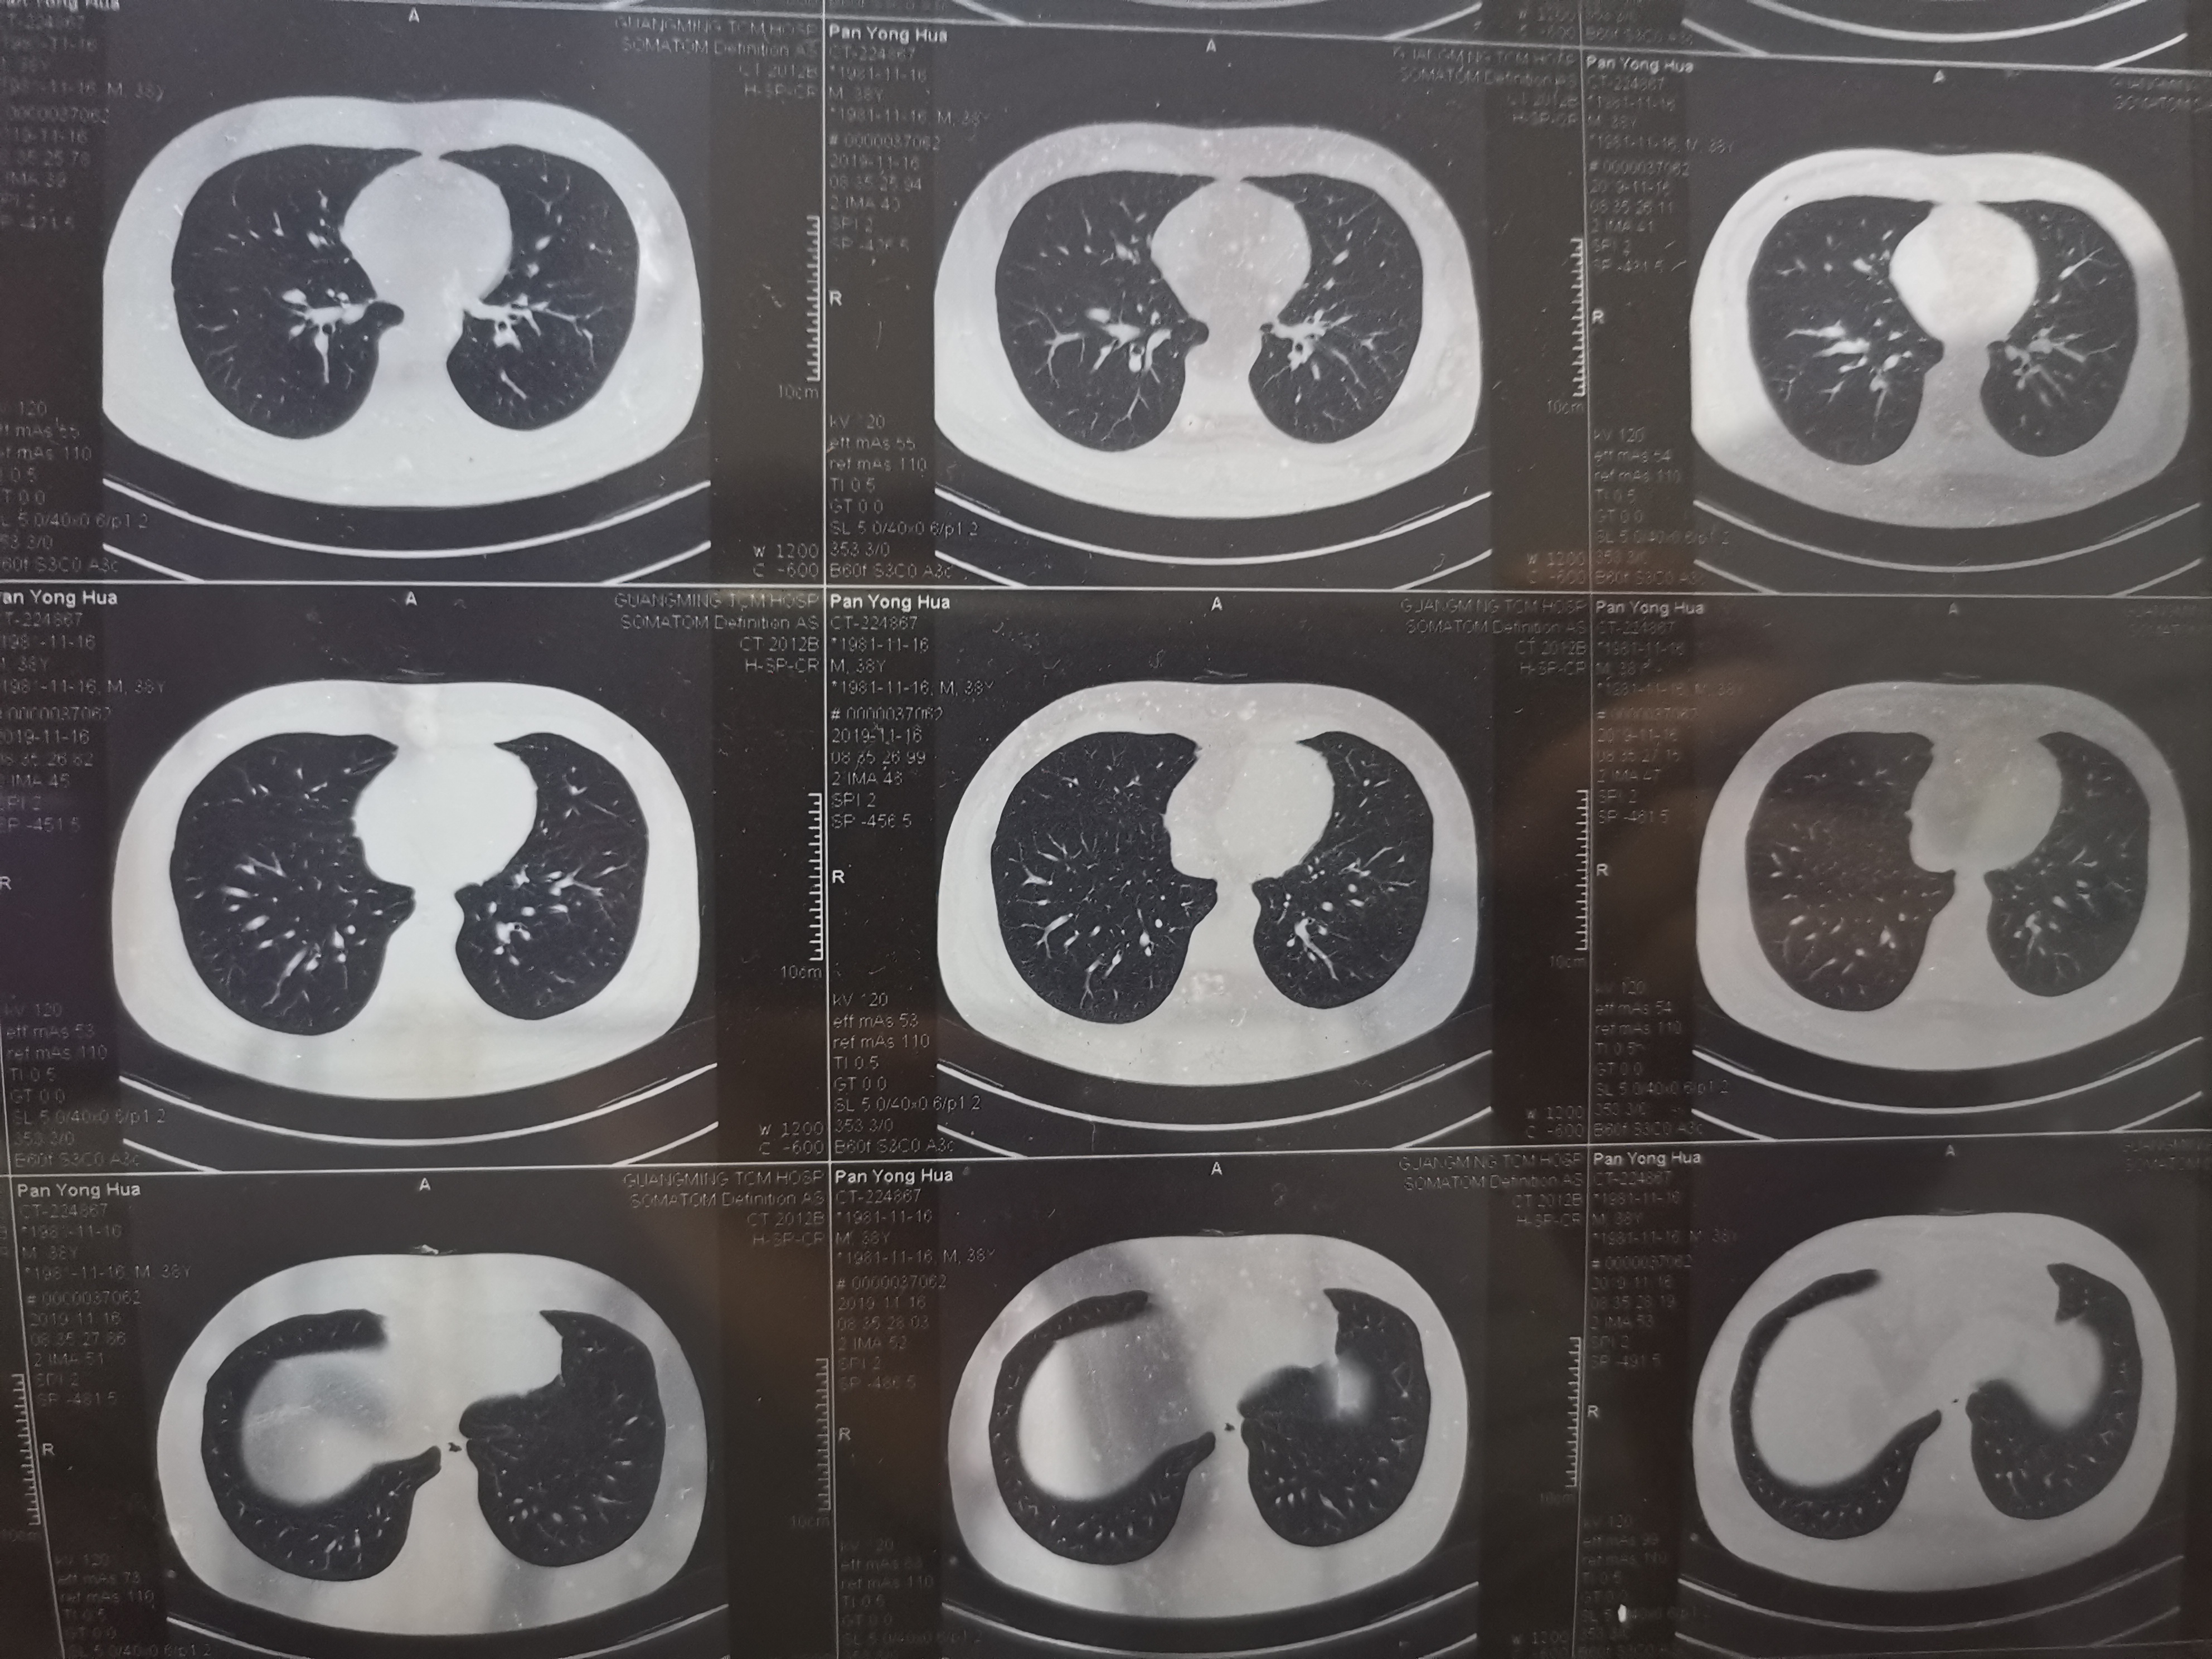

甄先生今年56,已经有很多年吸烟的习惯了,尽管知道吸烟有害身体,但始终戒不掉,最终也就放弃了。不过吸烟会增加患肺癌的风险,所以老甄心理也是悬着一根弦,每年体检都格...